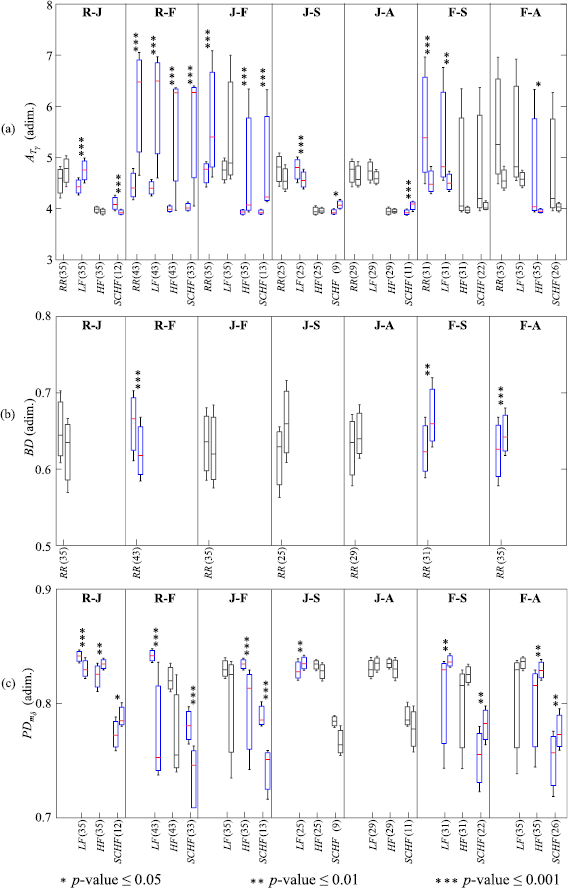

Those AMIF-based parameters that revealed statistically significant differences between relax and the different emotions or between pairs of emotions are presented in figure 4. In this figure, boxplots are shown in terms of median and interquartile ranges as first and third quartile:  (figure 4(a) for

(figure 4(a) for  = {RR, LF, HF, SCHF}; BD (figure 4(b) analysed on RR(t); and

= {RR, LF, HF, SCHF}; BD (figure 4(b) analysed on RR(t); and  (figure 4(c) for

(figure 4(c) for  = {LF, HF, SCHF}.

= {LF, HF, SCHF}.

Figure 4. Boxplots of the parameters derived from the AMIF: (a)  for

for  = {RR, LF, HF, SCHF}; (b) BD analysed on RR(t); and (c)

= {RR, LF, HF, SCHF}; (b) BD analysed on RR(t); and (c)  for

for  = {LF, HF, SCHF}. Only compared elicitations with some statistically significant differences are presented: relax and joy (R-J), relax and fear (R-F), joy and fear (J-F), joy and sadness (J-S), joy and anger (J-A), fear and sadness (F-S) and fear and anger (F-A). Statistical significance is denoted by * for p -value

= {LF, HF, SCHF}. Only compared elicitations with some statistically significant differences are presented: relax and joy (R-J), relax and fear (R-F), joy and fear (J-F), joy and sadness (J-S), joy and anger (J-A), fear and sadness (F-S) and fear and anger (F-A). Statistical significance is denoted by * for p -value  0.05, ** for p -value

0.05, ** for p -value  0.01 and *** for p -value

0.01 and *** for p -value  0.001, all showed sensitivity, specificity and accuracy values

0.001, all showed sensitivity, specificity and accuracy values  70% and AUC index

70% and AUC index  0.70. The number of the analysed subjects is indicated in parentheses.

0.70. The number of the analysed subjects is indicated in parentheses.

Standard image High-resolution imageIn table 4, p -value, AUC and accuracy values are remarked in bold type for those AMIF-based parameters that revealed statistically significant differences between the emotional states studied. The presented emotion conditions were those which revealed statistically significant differences.

Regarding the ability of the AMIF parameters to discriminate emotions, the total areas (figure 4(a),  was the only parameter capable of statistically distinguishing joy and anger among all the studied parameters derived from the AMIF. This result shows the importance of redefining the boundary of the HF band for a correct evaluation of physiological changes of the ANS (Goren et al 2006, Valderas et al 2019). Fear revealed a greater median value than any other emotion. Note that an enlargement of the area under the AMIF curve indicates a better predictability of future heart beats, and therefore, a lower complexity (Boettger et al 2008).

was the only parameter capable of statistically distinguishing joy and anger among all the studied parameters derived from the AMIF. This result shows the importance of redefining the boundary of the HF band for a correct evaluation of physiological changes of the ANS (Goren et al 2006, Valderas et al 2019). Fear revealed a greater median value than any other emotion. Note that an enlargement of the area under the AMIF curve indicates a better predictability of future heart beats, and therefore, a lower complexity (Boettger et al 2008).

Evaluating the beat decay BD (figure 4(b), fear presented smaller median values than any other compared elicitation. Furthermore, this parameter was able to statistically distinguish between fear and relax, sadness and anger. However, the remaining pair of compared elicited states did not show such a clear pattern as fear. Additionally,  (figure 4(c) presented a similar tendency as the BD for fear with a smaller median value than any other elicitation state. The BD and

(figure 4(c) presented a similar tendency as the BD for fear with a smaller median value than any other elicitation state. The BD and  presented results with complementary information, and statistically significant values, and also adequate sensitivity, specificity, accuracy and AUC index.

presented results with complementary information, and statistically significant values, and also adequate sensitivity, specificity, accuracy and AUC index.

A complexity reduction is observed during fear elicitation as reflected by smaller BD, PD and

and  values together with a greater total area,

values together with a greater total area,  and

and  .

.